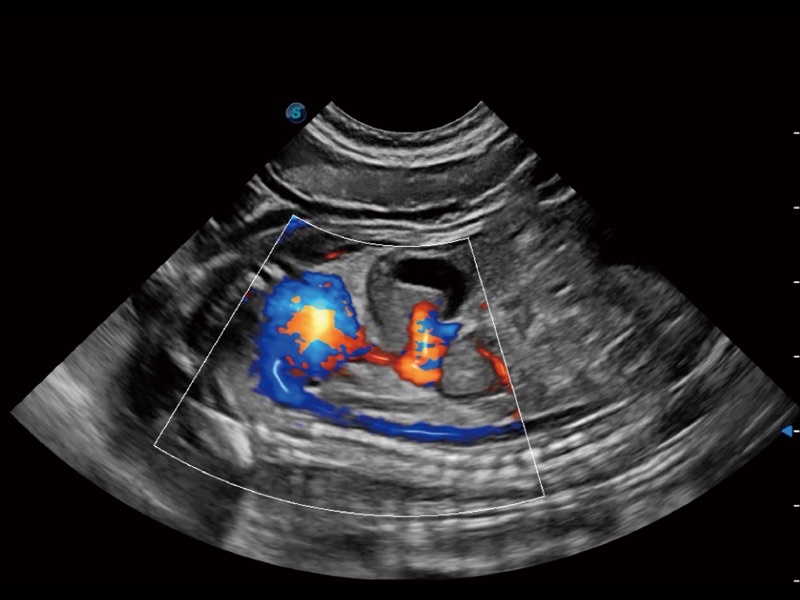

通过创新的 Matrix E自适应滤波器和超长时间域算法,极大提升超低速微细血流的检出能力,同时更精准地滤除软组织和噪声信号,为兽用医生提供以往无法通过常规血流获得的疾病诊断信息。

通过色彩血流和实时宽景相结合,可观察到完整的静脉或动脉的血流,方便医生检查。实时扫查过程中,如有任何操作失误也可以很容易地进行回扫擦除,而不会中断扫查。

ProPet 70专为动物医生设计,对不同的动物体型和生理结构作出了针对性的优化。通过动物影像专用软件,可满足个性化的应用需求,帮助动物医生获得更精确的诊断数据。